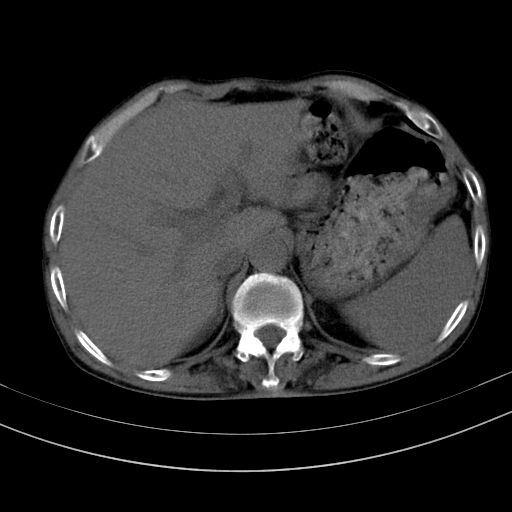

以下是引用dyqct在2010-1-9 17:56:00的发言:[br]考虑:1.双肾囊肿,左肾积水结石、旋转不良。[br] 2.右侧腹直肌血肿或纤维瘤。[br]肠道准备不好。做个增强。